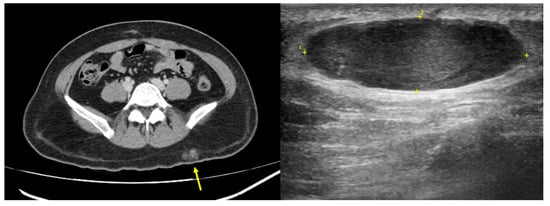

2.6. Imaging Examination